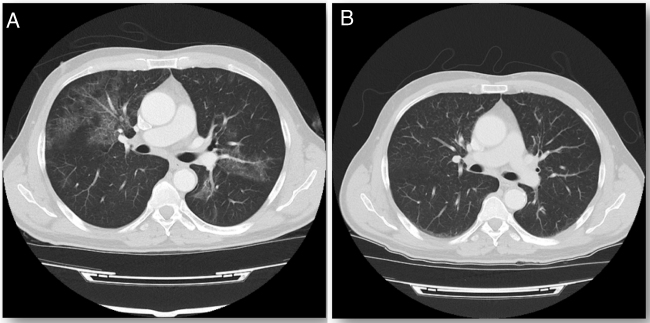

Comenzó terapia con GM-CSF inhalado siguiendo la pauta de administración empleada en el estudio de Tazawa et al.2, inicialmente a alta dosis (125 μg dos veces al día del primer al octavo día y descanso de noveno al décimo cuarto) durante seis ciclos de dos semanas, seguido de administración a baja dosis (125 μg una vez al día del primer al cuarto día con descanso del quinto al décimo cuarto) durante seis ciclos de dos semanas. Al finalizar el tratamiento mejoró la disnea y la tos, con mínima expectoración. A los dos meses la tomografía computarizada de tórax evidenció la desaparición completa de los infiltrados (imagen 1), junto con normalización de la DLCOc (82%) que se mantiene hasta la actualidad.

Imagen 1.

A) Tomografía computarizada (TC) de tórax con contraste en el momento del diagnóstico. B) TC de tórax con contraste a los dos meses de finalizar el tratamiento.